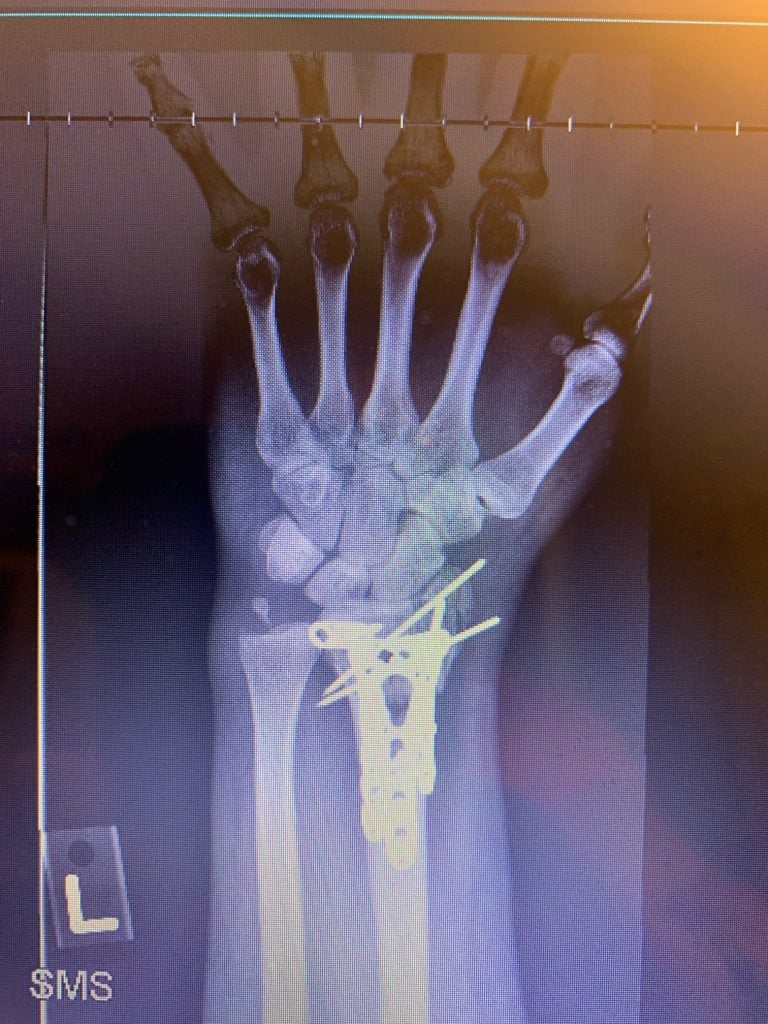

In the recovery room after surgery, Dr. Daluiski said that everything went well, even though it was a very severe accident. He inserted multiple plates and screws to help set my wrist (see photo 4). It was pretty painful for 2-3 days after surgery, but after that my wrist began to feel progressively better. I saw Dr. Daluiski about one week after the surgery and he said everything looked great so far (see photo 5 and 6). I was amazed that my wrist began to look like a normal wrist and that I was able to begin performing gentle range of motion exercises with the occupational therapists at the hospital. About six weeks after the surgery, I had a second surgery to remove some of the hardware in my wrist. The second surgery also went very smoothly. Throughout this process, I continued working with the occupational therapists to regain the motion and strength in my wrist.